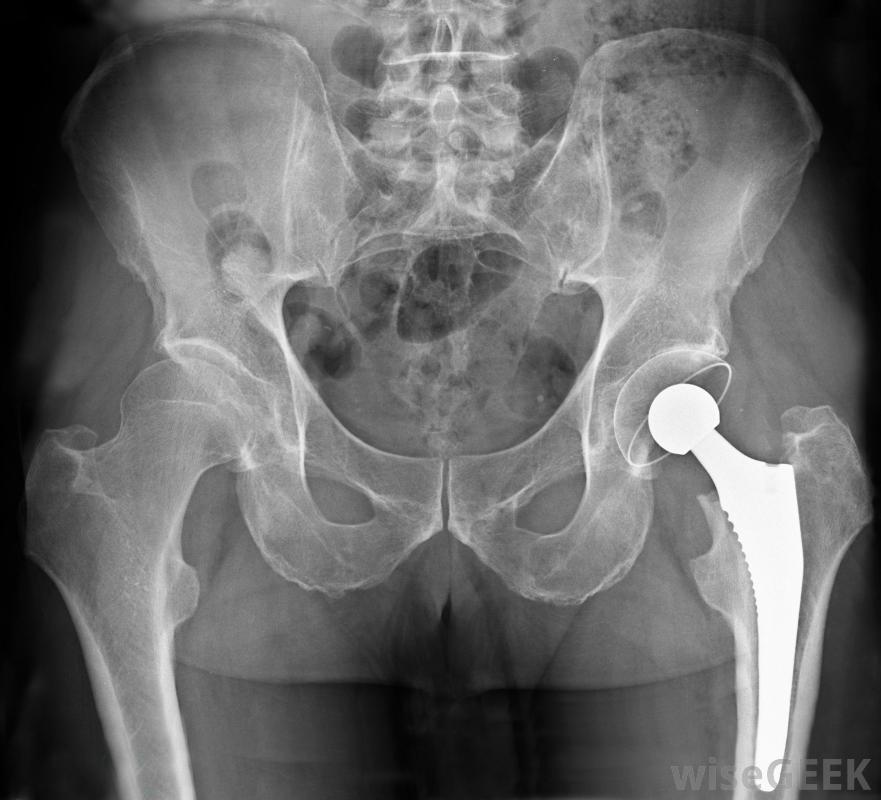

骨盆区域的X光片,显示一个金属置换髋关节。唇部位于髋关节的关节窝处髋部唇部撕裂通常由骨科医生诊断。医生可以测试患者髋关节的运动情况,以检查是否存在不规则情况。如果怀疑是唇部撕裂,医生很可能会要求磁共振成像(MRI)扫描,以获得清晰的图像和关于撕裂位置和大小的信息唇裂的治疗方法包括运动后休息,物理治疗以增加柔韧性,使用消炎药物来减少髋关节周围和髋关节周围的炎症或者髋关节活动范围的减小可能会导致髋关节的关节镜手术。这种手术通常是通过髋关节外侧的两个小切口来完成的。骨科医生使用特殊的器械来清洁和修复髋关节唇的受伤区域关节镜下髋关节手术的恢复需要6周时间,通常包括物理治疗。成功的手术可以修复唇部的撕裂或磨损区域,使表面光滑。康复后,患者通常可以恢复髋关节的全部活动范围,尽管有一些迹象表明唇撕裂可能会导致髋关节炎,但目前还没有明确的证据,专家们一致认为有必要进一步研究唇裂的长期影响